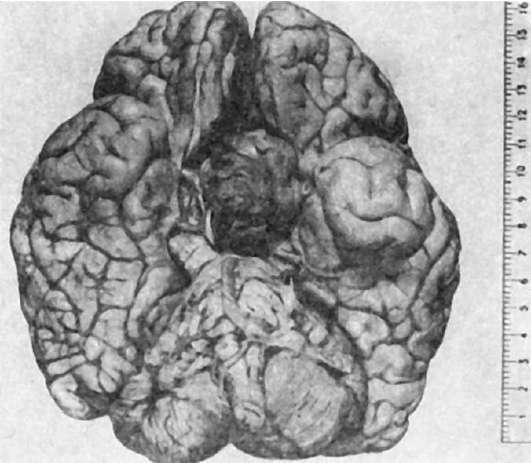

Рис.